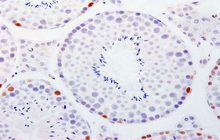

- General and specialized tissue and cell staining

- Immunocytochemistry (ICC) technique

- Immunohistochemistry (IHC) technique

Histological methods includes sample processing in the pathology laboratory, preparation of the slide and its examination under a microscope, sample fixation, molding, microtome cutting, staining and assembly of the slides.